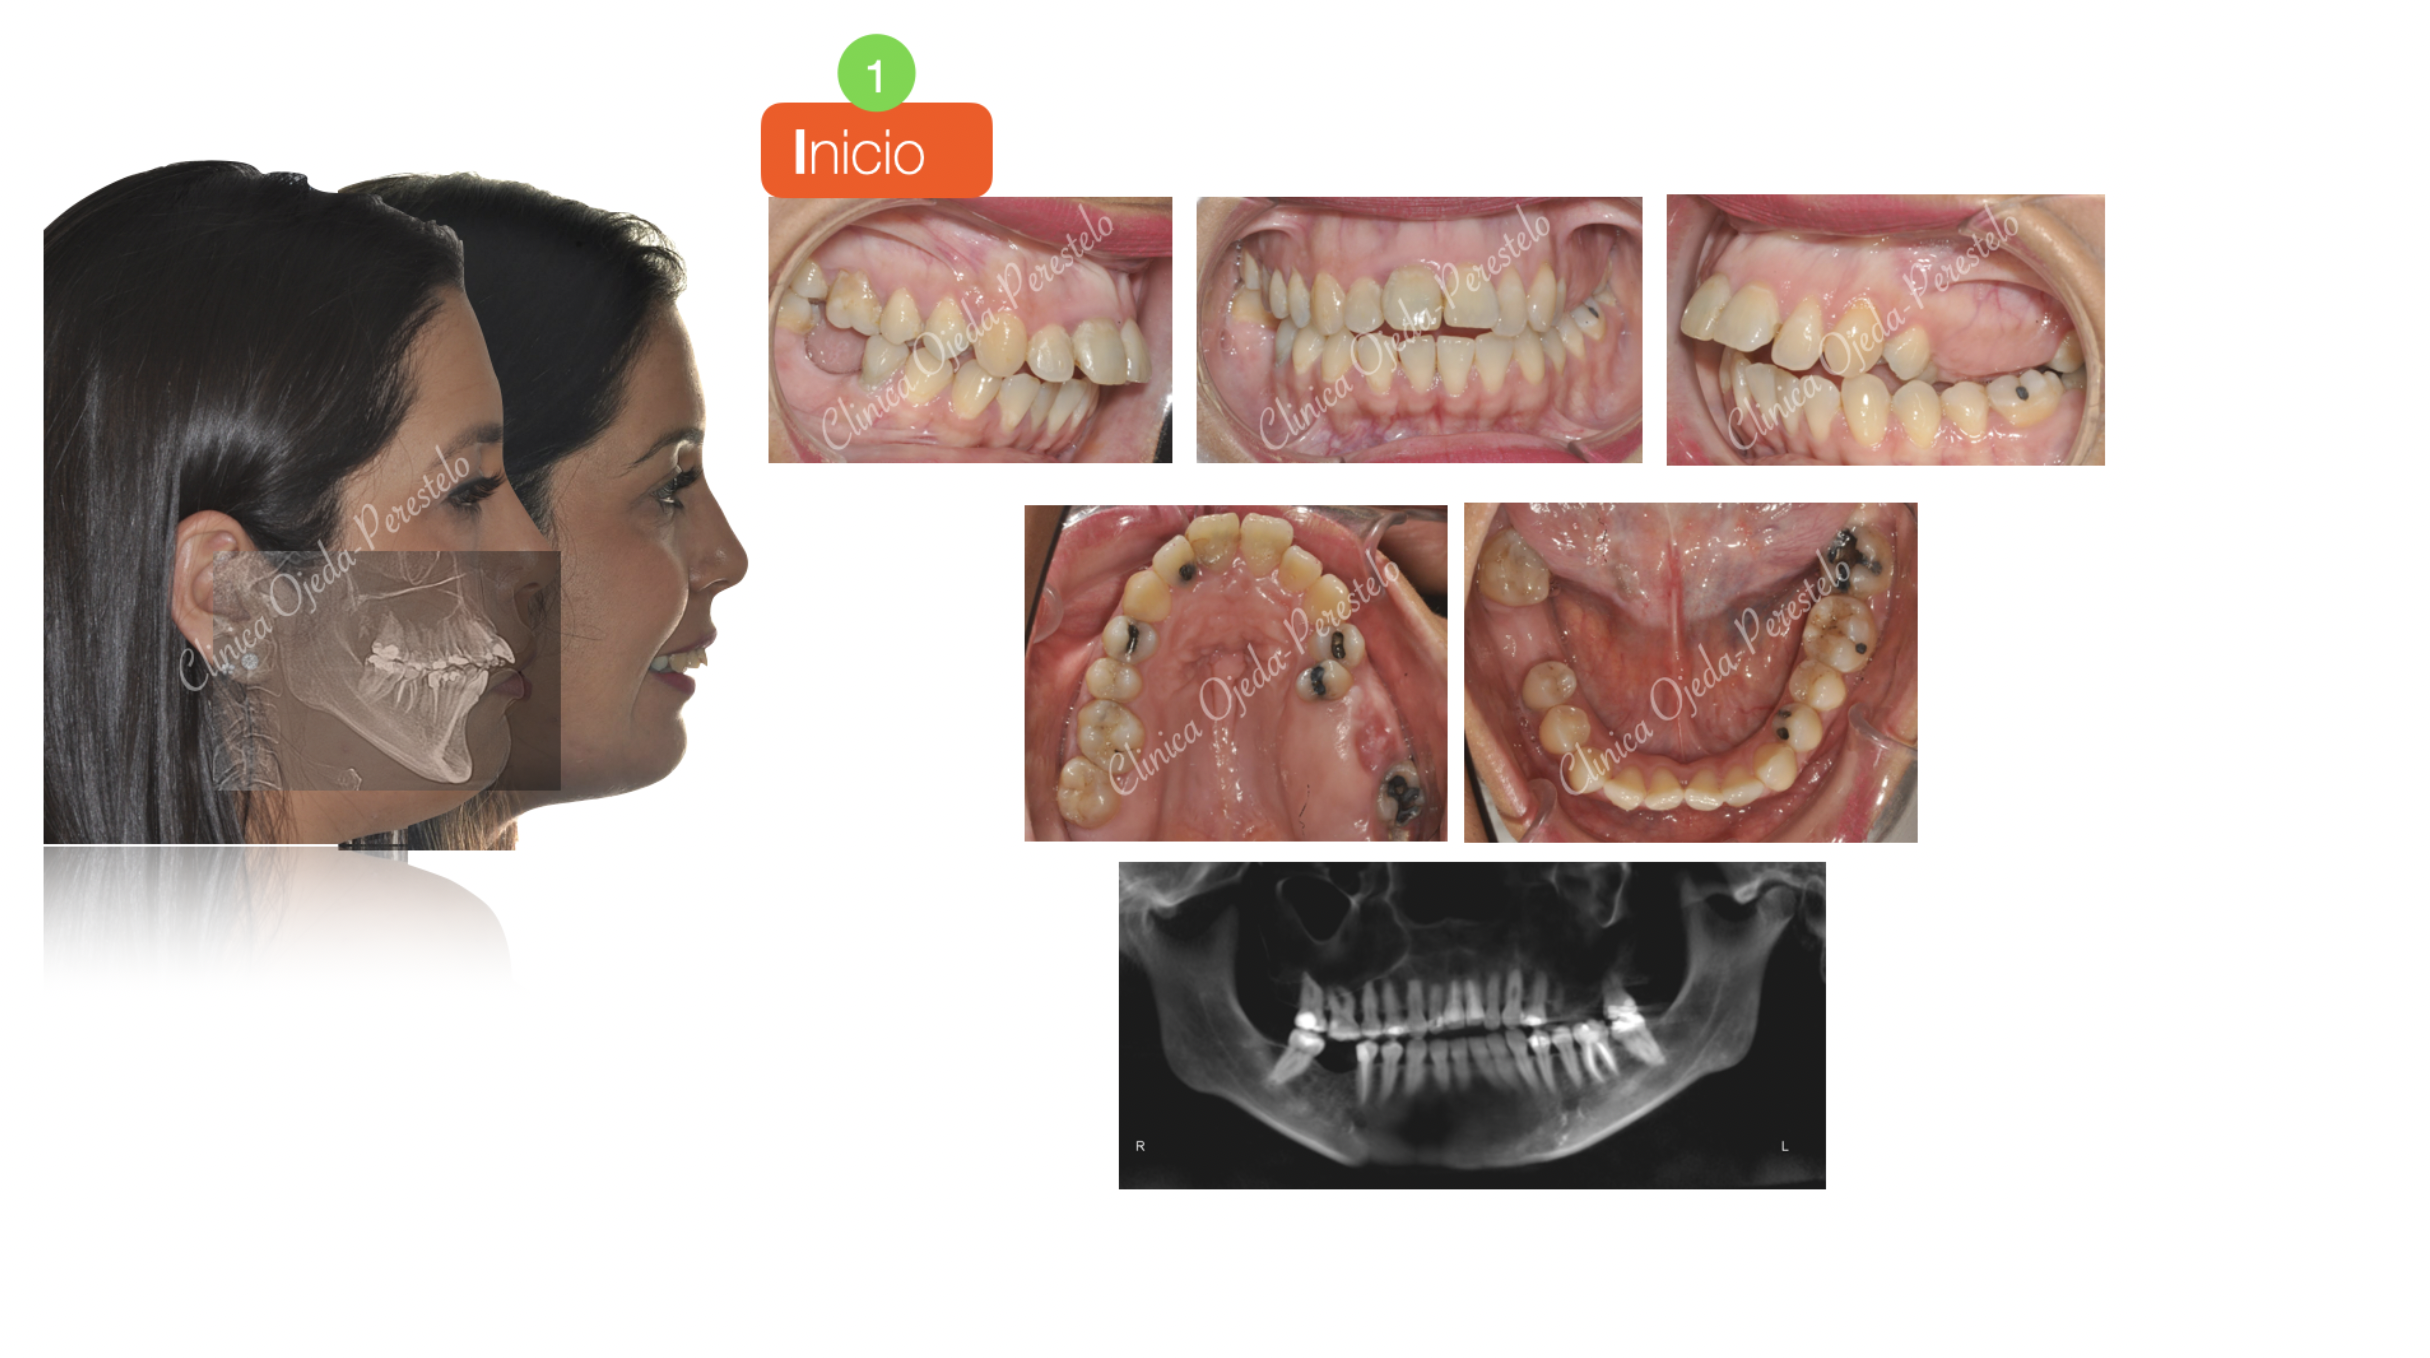

En la actualidad todos aquellos pacientes subsidiarios de Cirugía Ortognática pueden verse beneficiados de realizar un tratamiento ortodóncico-quirúrgico con Alineadores Transparentes. Presentamos la evolución de una paciente tratada con alineadores transparentes y  Cirugía de  avance mandibular en 4 etapas diferenciadas:

-1. Alineacion/Nivelacion I + Cierre de Mordida facilitada por TADS.